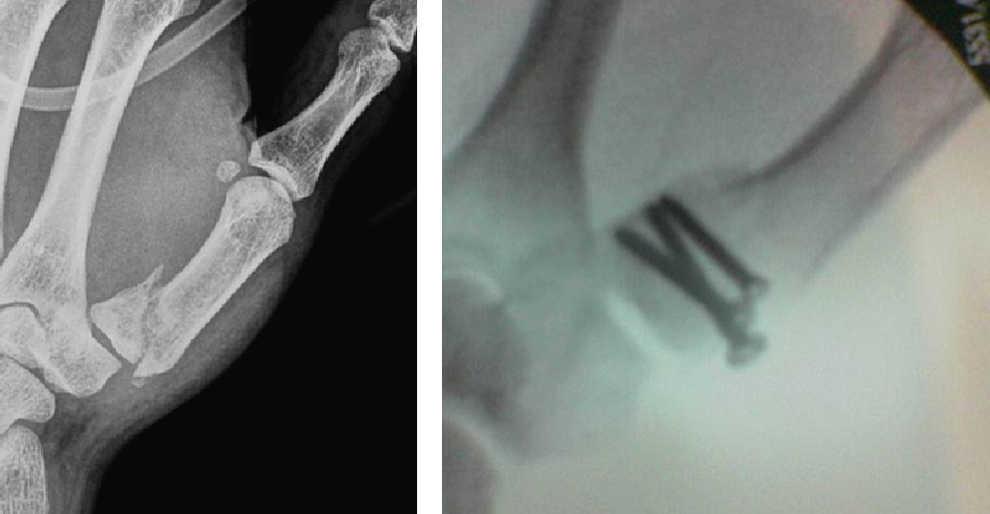

Las reducciones radiográficas de la fractura fueron aceptables desde el punto de vista anatómico en 78 (92,85%) casos. En 3 (3,57%) pacientes con fractura articular de la base de la falange conminuta hubo defecto de reducción de la fractura con una superficie articular corregida, en 2 pacientes (2,38%) no se consiguió corregir perfectamente la superficie articular debido a la gran conminución y a que los fragmentos óseos eran muy pequeños (referidos como malos resultados) y en un (1,19%) paciente con fractura de la falange proximal del cuarto dedo quedó una ligera diástasis del foco de fractura, tras tener un traumatismo en el dedo la fractura se desplazó y se lo intervino para colocarle una placa y tornillos (referido como mal resultado [figura 5).

Figura 5. Fractura oblicua larga de la falange proximal del dedo anular de la mano derecha. Fracaso de osteosíntesis percutánea. Nueva osteosíntesis con placa y tornillos.

Las complicaciones imputables a la técnica solamente se han observado en 3 pacientes, en uno de ellos la fractura no quedó suficientemente estable y al recibir el paciente un traumatismo sobre el dedo se desplazó y movió los tornillos, por lo que precisó una nueva intervención mediante osteosíntesis con placa y tornillos, con buenos resultados posteriores (figura 5). En 2 pacientes no se consiguió la reducción anatómica articular adecuada, aunque probablemente si se hubiera intentado la reducción abierta el resultado habría sido igual o peor debido al tamaño reducido y a la gran conminución de los fragmentos óseos.